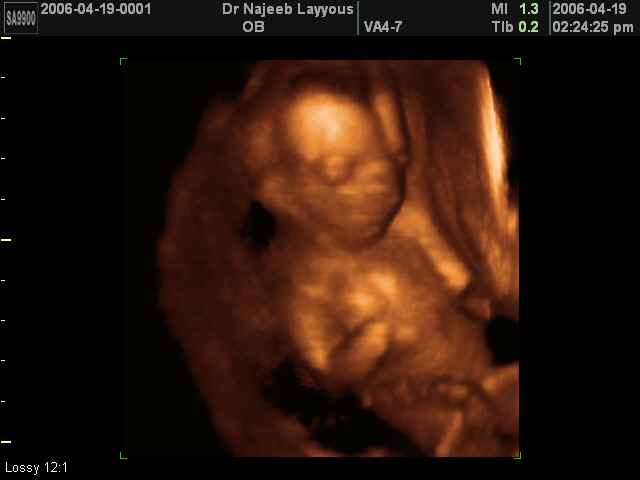

- Fetal Behavior Ultrasound Photos

Ultrasound Photos in 3D showing Fetal Behavior Inside the uterus | Dr N Layyous